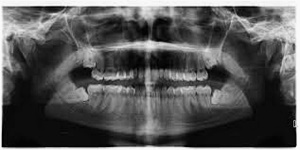

우리가 사랑니라고 부르는 것은 큰 어금니 중 세 번째 위치에서 제일 마지막에 나오는 치아입니다. 사랑니가 나올 때에는 첫사랑을 하듯이 아프다고 하여 붙여진 이름이라고 하는데요. 다른 이름으로는 ‘지치’라고 합니다. 지치는 사리를 분별할 수 있는 지혜가 생긴다는 뜻입니다.

사랑니는 보통 큰 어금니와 비슷하게 생겼습니다. 사랑니의 형태나 크기는 매우 다양하다고 하는데요. 보통의 어금니 보다 깊이 나기 때문에 빼기 어렵거나 절개를 통해 힘들게 빼야 하는 경우가 많습니다. 원래 사랑니는 음식물을 갈아 내기 위한 용도라고 하는데요. 이것은 치아의 퇴화 현상이라고 생각하시는 분들도 많이 계십니다.